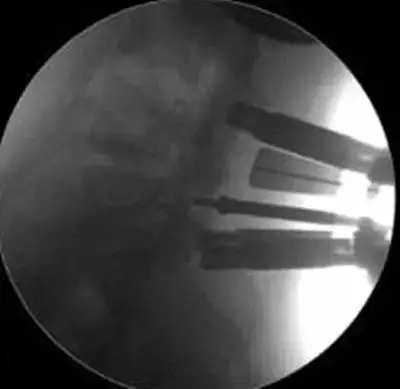

劉志安副院長所說的“微創(chuàng)小切口”就是通道下髓核摘除植骨融合經(jīng)皮內(nèi)固定術(shù)。其原理就是利用MIS-TLIF技術(shù)微創(chuàng)治療腰椎疾病,不但能達(dá)到開放手術(shù)的效果,且切口及創(chuàng)傷為開放切口的1/3,術(shù)中出血量少,患者術(shù)后可以恢復(fù)更快。

劉志安副院長將具體的手術(shù)過程向朱先生做了介紹,朱先生也同意了這個(gè)“微創(chuàng)小切口”手術(shù)。于是在術(shù)前的精心準(zhǔn)備之后,劉志安副院長協(xié)同其他醫(yī)護(hù)人員為朱先生進(jìn)行了手術(shù)。術(shù)后,朱先生的切口愈合良好,腰部疼痛消失,小腿麻木感也漸漸緩解。“手術(shù)后傷口略微有點(diǎn)痛,現(xiàn)在已經(jīng)完全不痛了,這種輕松的感覺已經(jīng)好久沒有了,真是萬分感謝劉院長。”在病房內(nèi),一臉笑容的朱先生如是說。

據(jù)劉院長介紹,MIS-TLIF技術(shù)是經(jīng)椎旁肌間隙入路運(yùn)用脊柱內(nèi)鏡或?qū)S猛ǖ佬醒甸g盤切除、椎管減壓、植骨內(nèi)固定術(shù),是一項(xiàng)應(yīng)用廣泛、技術(shù)成熟的脊柱微創(chuàng)手術(shù)方法。本技術(shù)可以完成與傳統(tǒng)手術(shù)完全相同的椎間盤切除、椎間植骨融合內(nèi)固定等操作。手術(shù)切口一般3-5厘米,本手術(shù)方式可有效避免傳統(tǒng)手術(shù)對腰背肌肉的損傷,患者術(shù)后腰背部疼痛輕、恢復(fù)快,手術(shù)效果優(yōu)于傳統(tǒng)手術(shù),治療后1-3天即可下床活動(dòng)。本技術(shù)適于大部分的腰椎間盤突出癥、腰椎管狹窄癥、腰椎滑脫癥等。